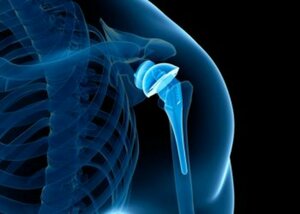

Shoulder Replacement